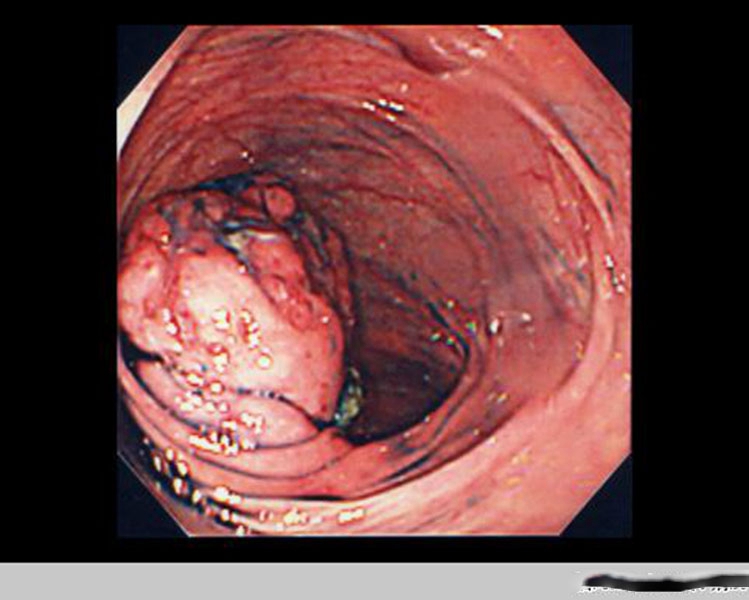

直腸腫瘤惡性腸鏡